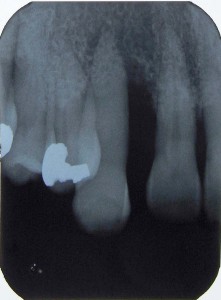

術前